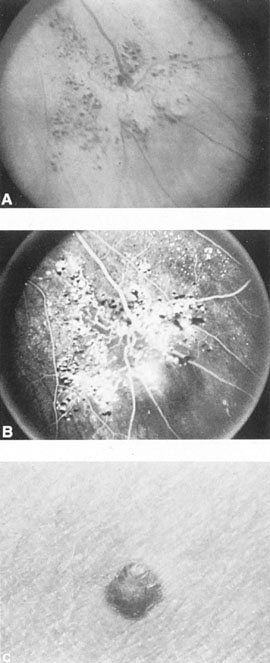

Anterior segment hypoxia may include protein flare and cells in aqueous, corneal edema, glaucoma, iris rubeosis, rapidly progressive cataract, and venous statis retinopathy, that is, an hypoxic eyeball syndrome. Lesser degrees of congestion with mild conjunctival arterialization (Fig. 15), ocular hypertension, and small abduction defect all hint at the slower flow, lower pressure situation that accrues usually spontaneously with dural circulation fistulas.104,106 Bruit is less likely.

Fig. 15. Dilated tortuous conjunctival vessels in a 63-year-old woman with a presumed dural carotid–cavernous fistula. She presented with a 2-week history of “red eye,” mild retroorbital headache, and double vision. On examination, a left sixth nerve paresis, 3 mm of proptosis, a faint orbital bruit, and slightly elevated intraocular pressure were found. All signs and symptoms resolved spontaneously in 6 weeks, while angiography was being contemplated.

Although the clinical constellation previously described implies the great likelihood of carotid–cavernous fistula, definitive diagnosis depends on complete angiographic evaluation with selective opacification of bilateral internal and external carotid arteries, and vertebral circulation. Prominence of the superior ophthalmic vein is frequently detected on CT scan and MRI, and less frequently extraocular muscle enlargement and lateral bulging of the cavernous sinus are seen by MRI.110 Standardized orbital echography regularly confirms enlargement of the superior ophthalmic vein and increased flow (Fig. 16),107,111 in both direct and indirect fistulas.

Fig. 16. Orbital ultrasonography. Transocular A-scans (left) and B-scans (right) in a carotid–cavernous fistula with dilated arterialized superior ophthalmic vein. Top left: Blurred spikes (arrow) within the dilated vessel indicate fast blood flow. Bottom left: Distinct spikes (arrows) from vessel walls, at low system sensitivity. Top right. Dilated superior ophthalmic vein (arrow), at low sensitivity setting. Bottom right: Cross-section of enlarged superior ophthalmic vein. (From Byrne SF, Glaser JS: Orbital tissue differentiation with standardized echography. Ophthalmology 90:1071, 1983.)

Therapy for carotid–cavernous fistula is directed toward relieving ocular symptoms, especially where visual loss is threatened, with the goal being thrombosis of the fistula with normalization of orbital hemodynamics. Various arterial ligatures, trapping procedures, controlled embolizations, and even direct intracranial attacks have been advocated, but the current trend indicates the great advance represented by intravascular closure using detachable balloon microcatheterization techniques (Fig. 17).106 Complications of these techniques include transient or fixed hemispheral dysfunction, cranial nerve palsies, field loss, and pseudoaneurysm formation.106,112 At least one case of acute angle-closure glaucoma was reported after transvenous embolization of a traumatic carotid–cavernous fistula necessitating emergency laser iridotomy.113 The complication was thought to arise from oculomotor palsy related to the coil pack within the ipsilateral cavernous sinus. However, complication rates are apparently low. In a series of 100 consecutive patients treated for direct carotid–cavernous fistula with detachable balloons, Lewis et al 114 reported an approximately 4% overall complication rate. Endovascular treatment of dural (indirect) carotid–cavernous fistulae is usually directed transvenously also using fibered platinum coils or, less often, liquid adhesive. A recent retrospective evaluation of 135 consecutive patients treated for dural carotidcavernous fistulae over a 15 year period by Meyers et al115 revealed low permanent morbidity of 2.3% and high 90% rate of clinical cure.

Fig. 17. A 32-year-old woman was accidentally shot in the right eye with a low-velocity missile. The initial recovery was excellent, except for loss of the right eye. Five days after the injury, left proptosis and bruit developed. Two weeks after the injury, she developed paralysis of the left sixth and fourth nerves, and visual acuity decreased to 20/400 (6/120) in her remaining (left) eye. An interventional neuroradiologic procedure was performed with complete return of function in the left eye. A: Left carotid arteriogram with immediate opacification of entire cavernous sinus (arrows). B: One-half second after (A) there was extensive filling of dural venous channels and orbital veins. C: Detachable flow-guided balloon (arrows) placed in the fistula under fluoroscopic control and opacified with contrast medium. D: Follow-up left carotid arteriogram after balloon (arrows) placement. The fistula was completely closed with preservation of carotid flow. (Courtesy of Dr. Charles Kerber.)

Spontaneous thrombosis of some fistulas does occur, especially with the slow-flow dural variety. In a series of 20 patients, 12 closed spontaneously within 3 months and 3 closed at between 6 to 18 months,116 whereas in other reviews closure rates range from 10% to 60%.106 Therefore, a period of observation may afford the least harmful management. Precise indications for intervention are unclear but surely include visual deterioration due to glaucoma, iris rubeosis or ischemic retinopathy, transient ischemic attacks, intolerable subjective bruit, or head or eye pain not otherwise amenable to conservative therapy. Halbach and co-workers117 suggested that increased intracranial pressure, rapidly progressive proptosis, visual loss, and varix-like distortion of the cavernous sinus itself all constitute indications for urgent intervention. We have seen a case of a young man with traumatic fistula and cavernous sinus enlargement to the point of intracranial compression of the ipsilateral optic nerve, with reversal of blindness after balloon occlusion, and Mirabel et al118 have reported a “giant suprasellar varix” of the superior petrosal sinus associated with a dural arteriovenous fistula. It bears repetition that few carotid–cavernous fistulas are life threatening and individual case assessment seems reasonable.